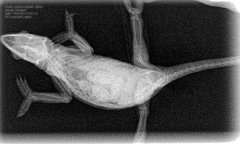

Aquí dejamos unos ejemplos reales:

Galería Radiografía digital